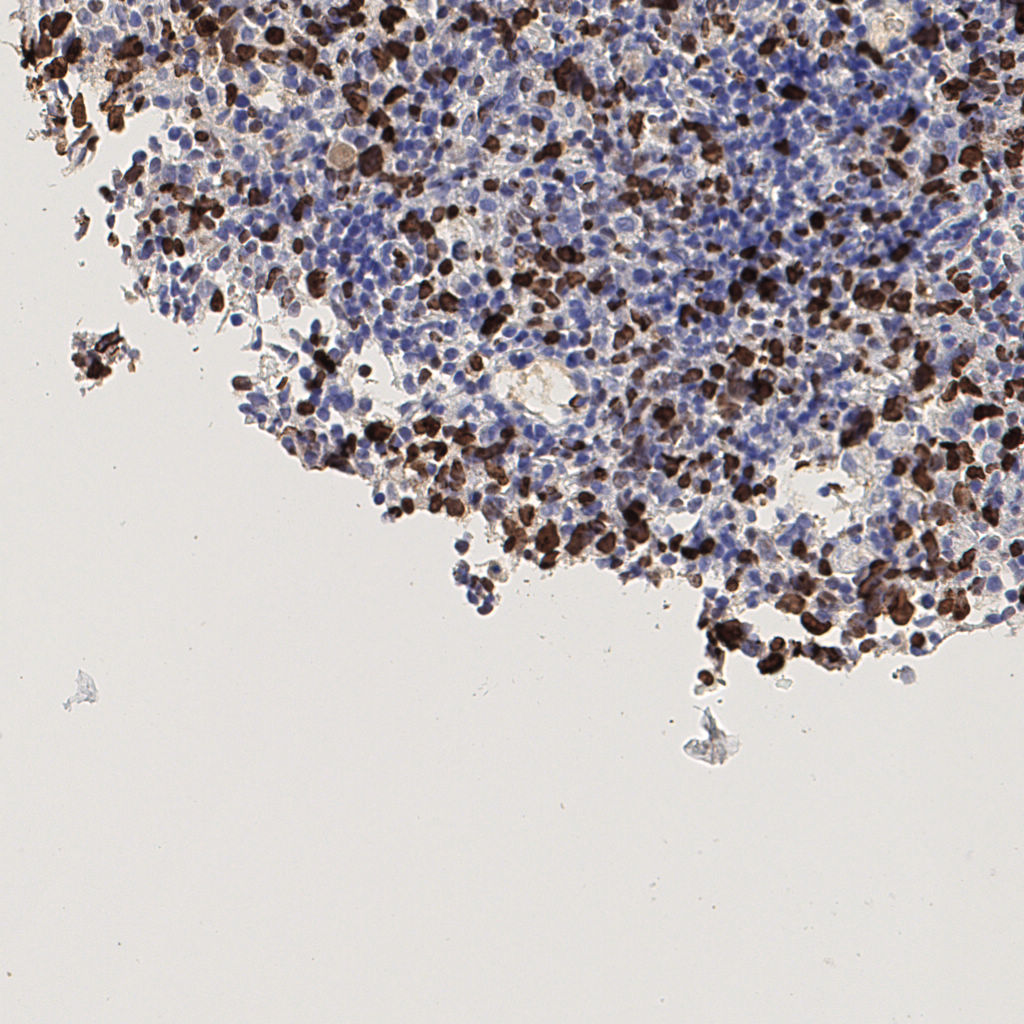

7.85%

Ki67 指数

阴 1104 阳 94